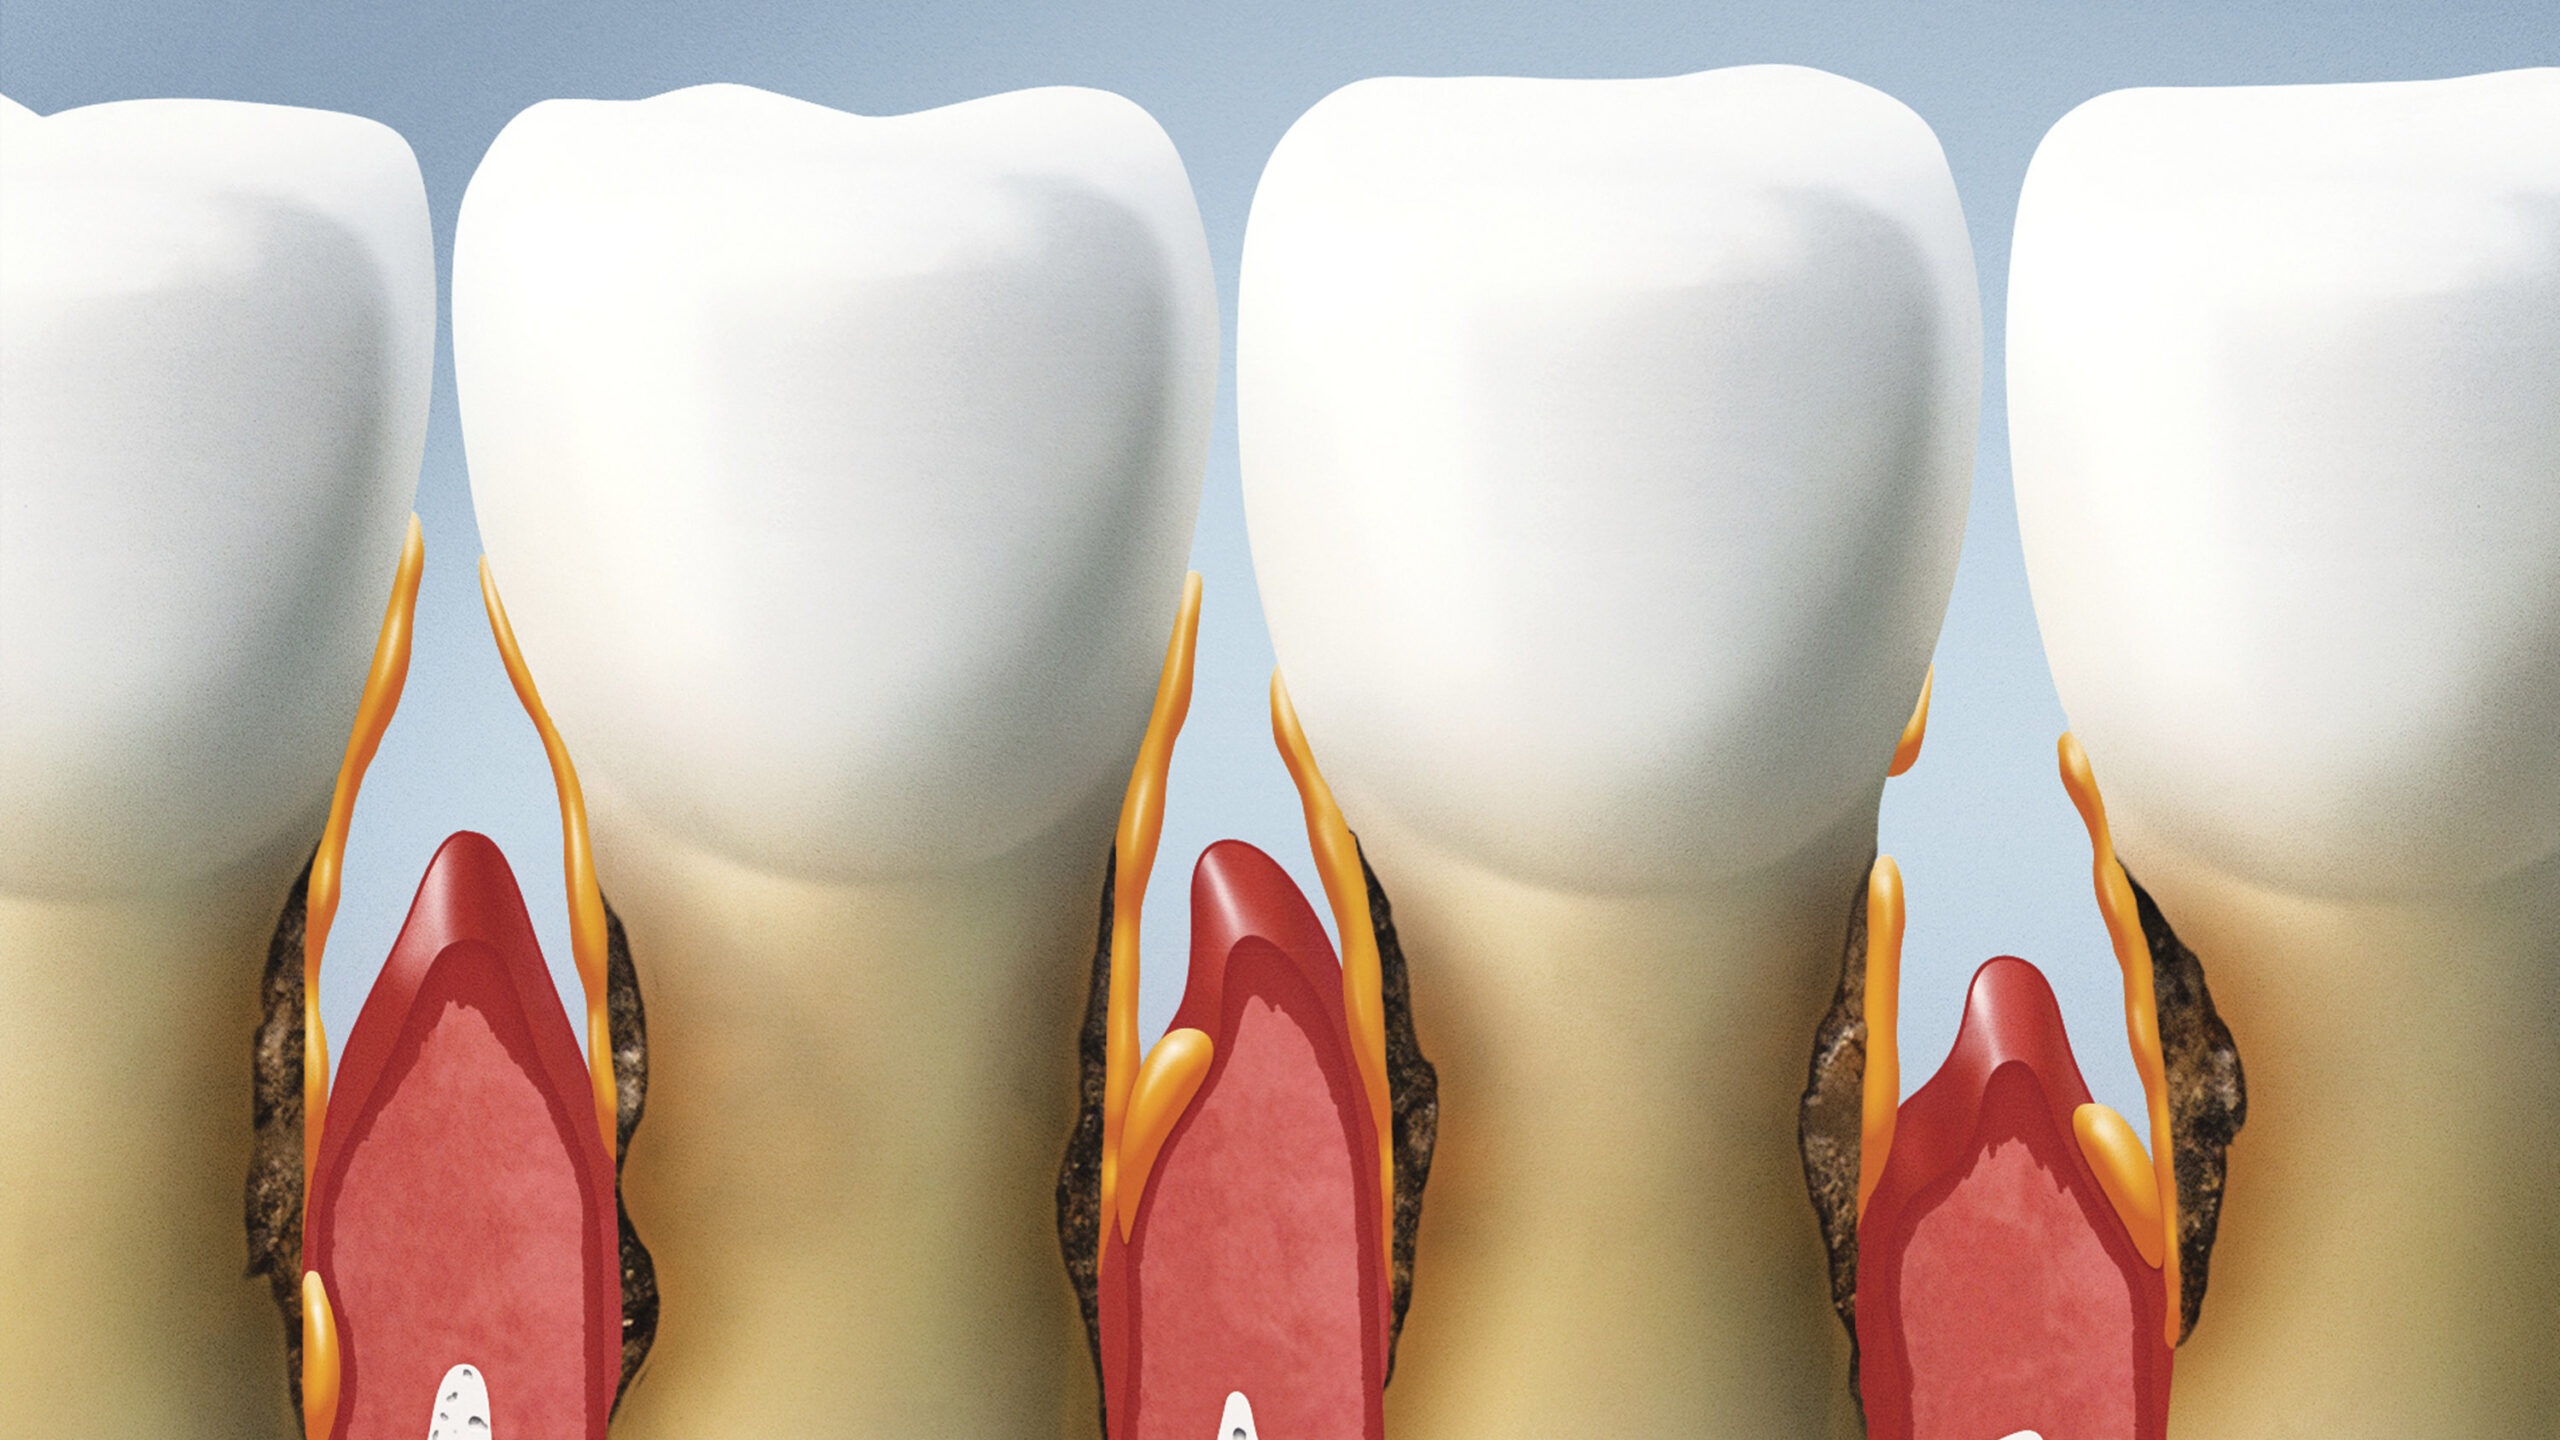

Este procedimento remove o tártaro endurecido e o biofilme bacteriano acumulado nas raízes dos dentes.

- Raspagem e Alisamento Radicular (RAR): Este é o ponto de partida. Seu dentista fará uma limpeza profunda para remover todo o tártaro e o biofilme bacteriano que se acumularam abaixo da linha da gengiva. O objetivo é deixar as raízes dos dentes o mais lisas possível para dificultar a adesão de novas bactérias. É um processo minucioso e essencial. Saiba mais sobre a importância dessa etapa em www.gov.br.

A base do tratamento para qualquer doença periodontal é a remoção mecânica das causas: placa bacteriana e cálculo (tártaro). A terapia não cirúrgica, que inclui a Raspagem e Alisamento Radicular (RAR), é o primeiro e mais importante passo. Ela visa criar um ambiente bucal limpo para que a gengiva possa cicatrizar e se reaproximar do dente.

Pense na RAR como uma limpeza profunda e detalhada. O dentista remove cuidadosamente todo o acúmulo de placa e tártaro, tanto na coroa do dente quanto nas raízes, abaixo da linha da gengiva. O alisamento radicular é a parte onde a superfície da raiz é polida para torná-la lisa, dificultando a aderência de novas bactérias. É um procedimento que pode exigir anestesia local, pois é feito em consultório.